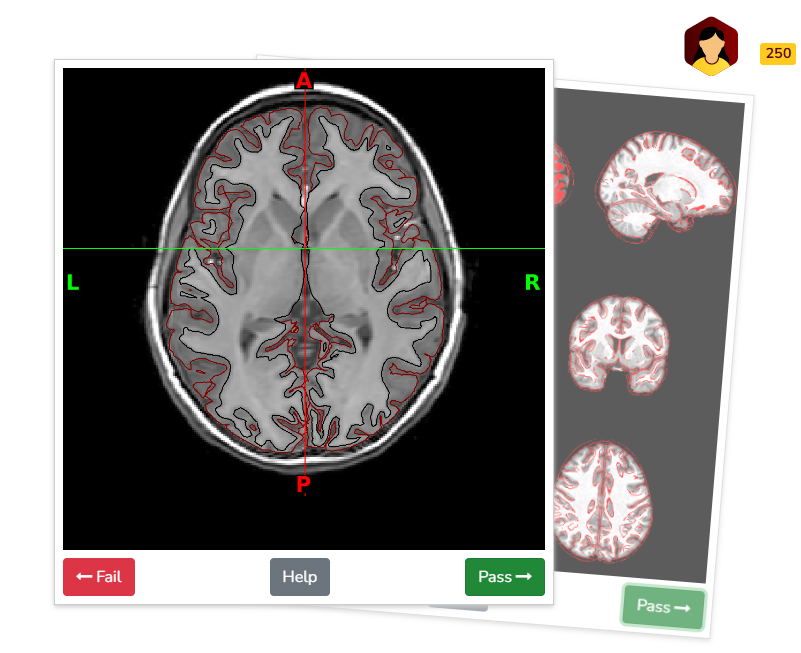

For structural QA, swipers are presented with image slices in coronal, axial, and sagittal planes to assess the accuracy of T1w and T2w surface delineations in differentiating gray and white matter. Images are derived from XCP-D visual reports.

In addition to surface delineation, structural QA also includes atlas registration quality, evaluated by overlaying delineations of the subject’s image onto the atlas, and vice versa. Swipes display nine T1w slices for visual inspection, with three slices per anatomical plane. Quality is assessed based on the alignment of the outer boundaries of the overlaid contours with those of the underlying image, ensuring minimal gaps or misalignments. Images are derived from XCP-D visual reports.

Example quality assessment of surface delineation on BrainSwipes platform (displaying brain in axial plane at level of basal ganglia/putamen):